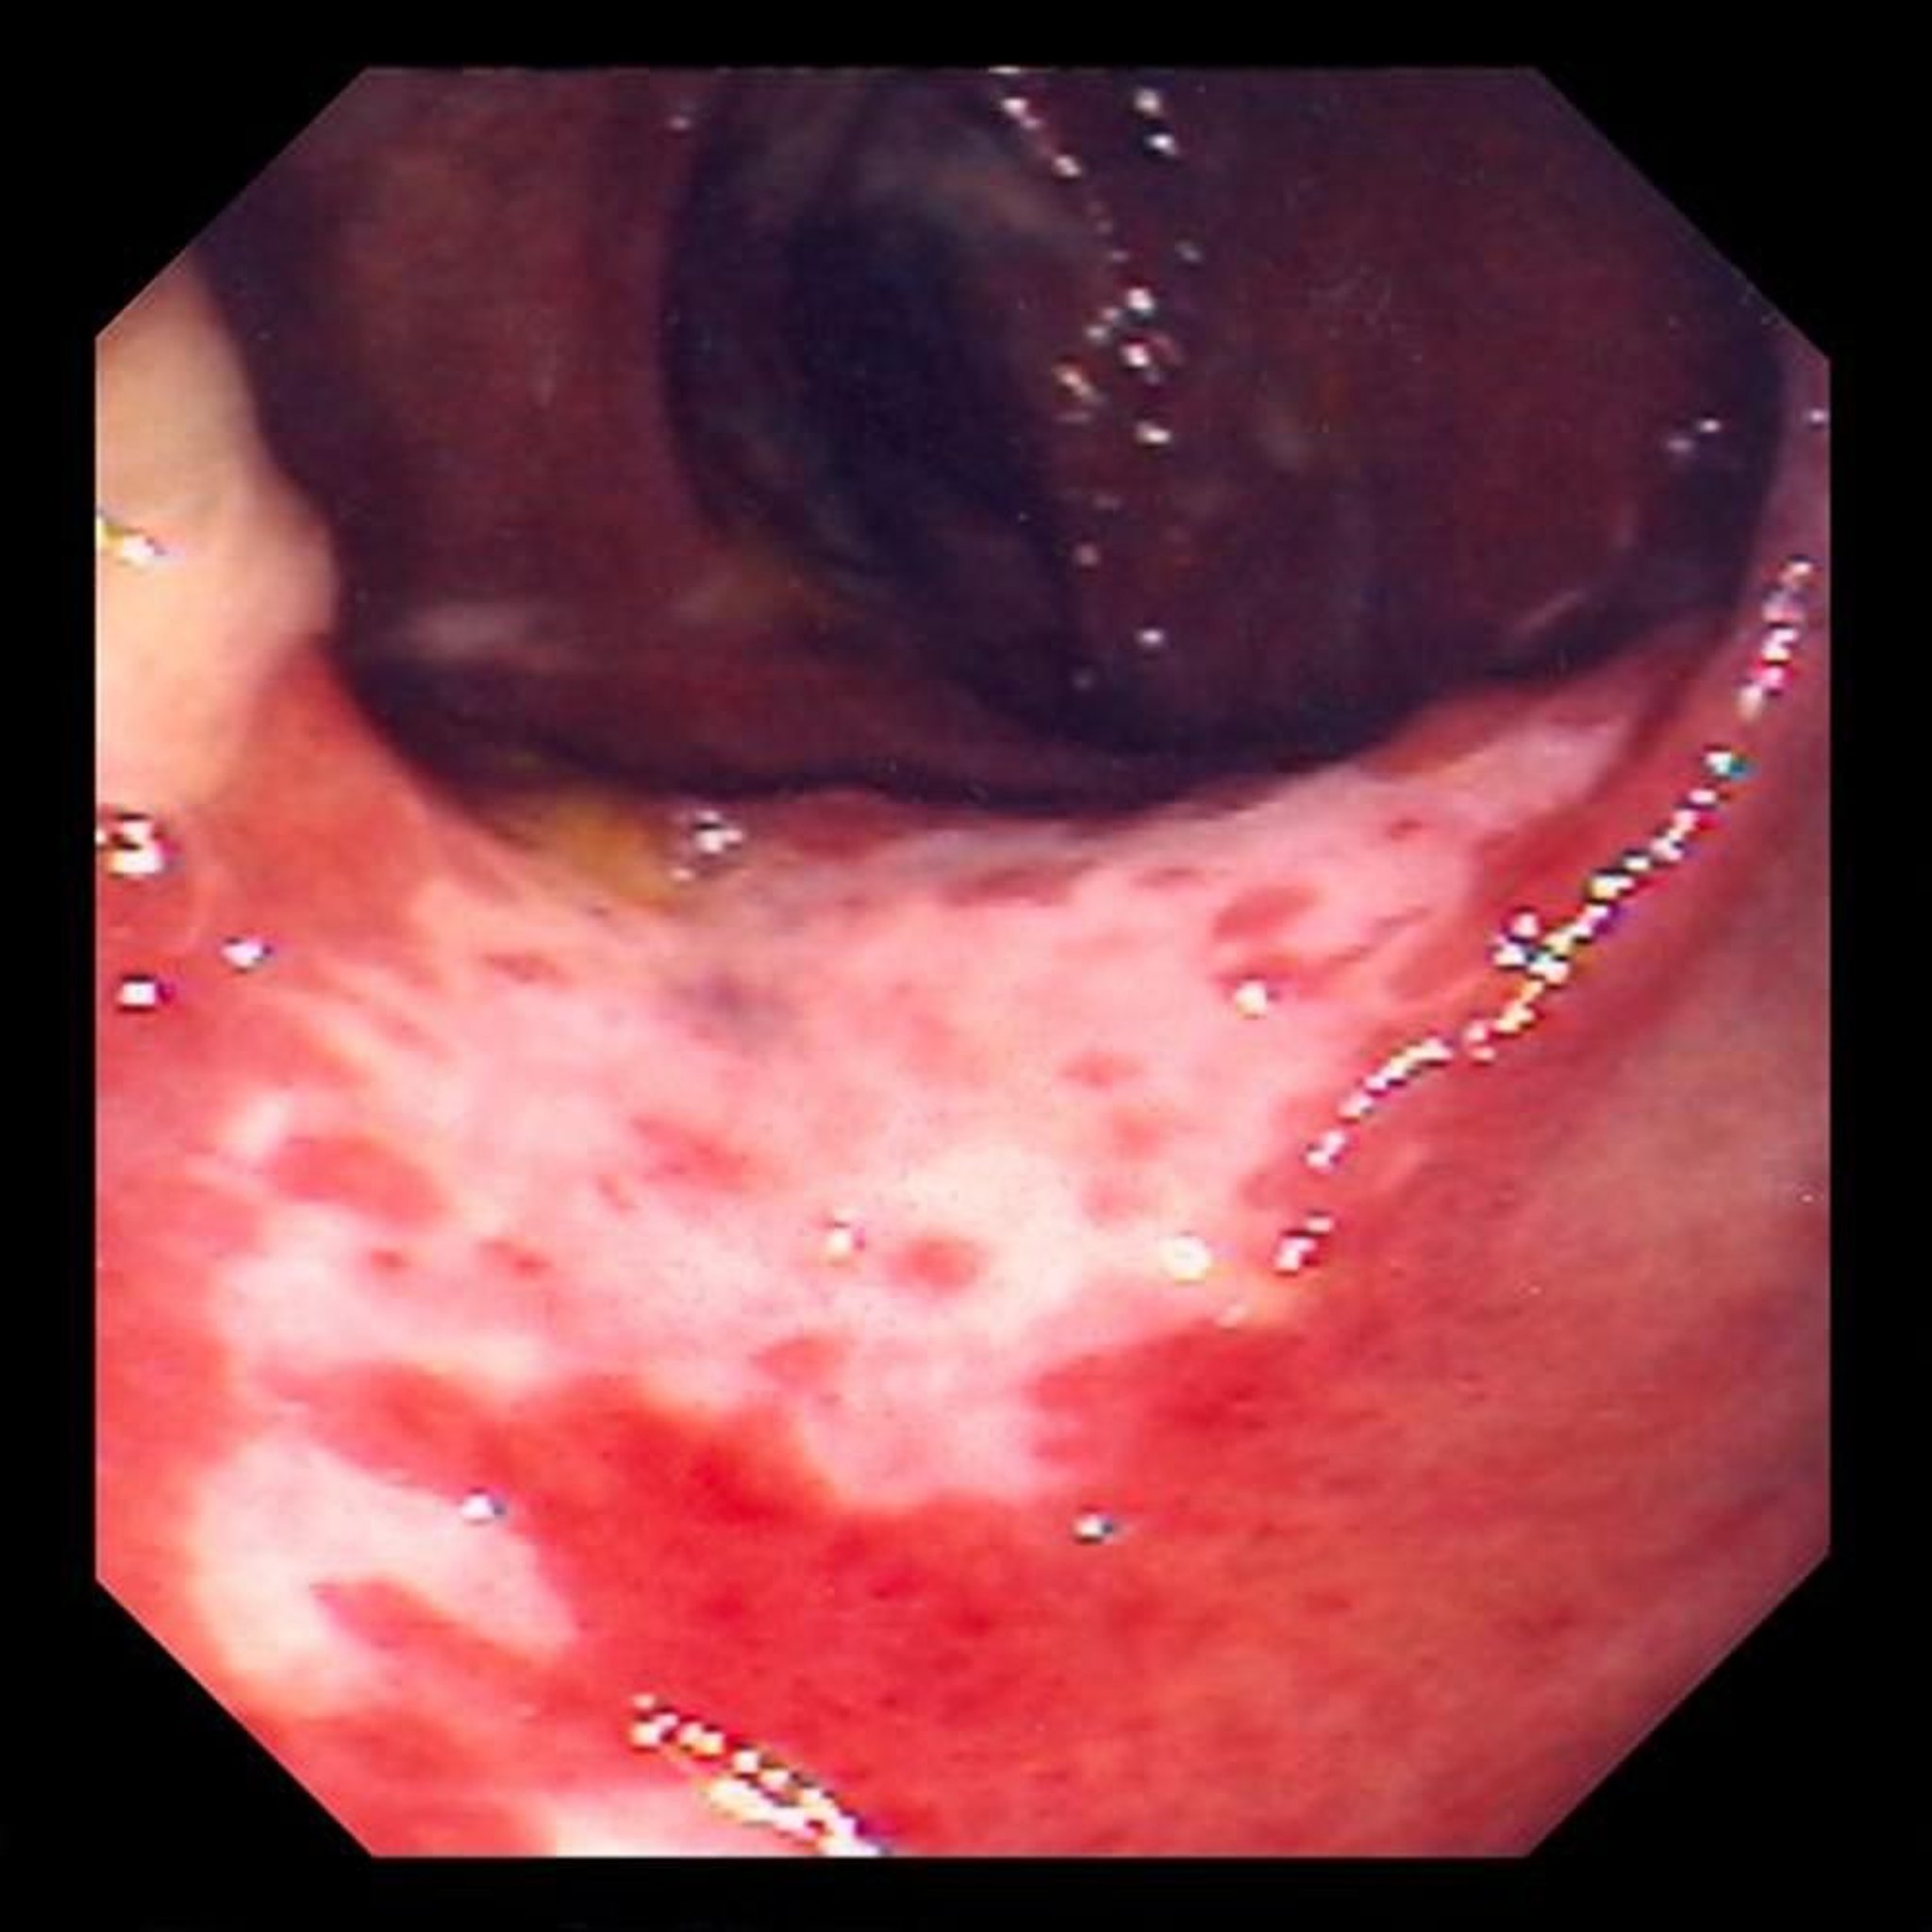

التهاب القولون الإقفاري (التنظير الداخلي)

تُظهر هذه الصورة ضررًا في بطانة الأمعاء بسبب انقطاع التروية الدموية.تبدو بطانة الأمعاء بلون أحمر، ومغطاة بقرحات (المناطق البيضاء).

Photo provided by David M.Martin, MD.